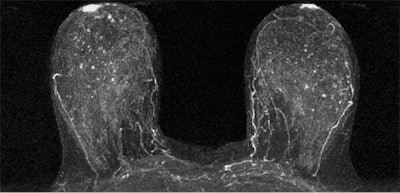

Researchers from the University of Washington found that women with an MRI assessment of mild, moderate, or marked background parenchymal enhancement (BPE) were nine times more likely to develop breast cancer than women with minimal BPE. In contrast, tissue density measured by both MR and mammography was not a statistically significant indicator.

BPE, however, was significantly linked to cancer: The women with mild, moderate, or marked background parenchymal enhancement made up the majority of the cancer cohort.

"We found that a significantly higher percentage of women in the cancer cohort had either mild, moderate, or marked BPE (78%) than did women in the control cohort (43%)," the authors wrote.